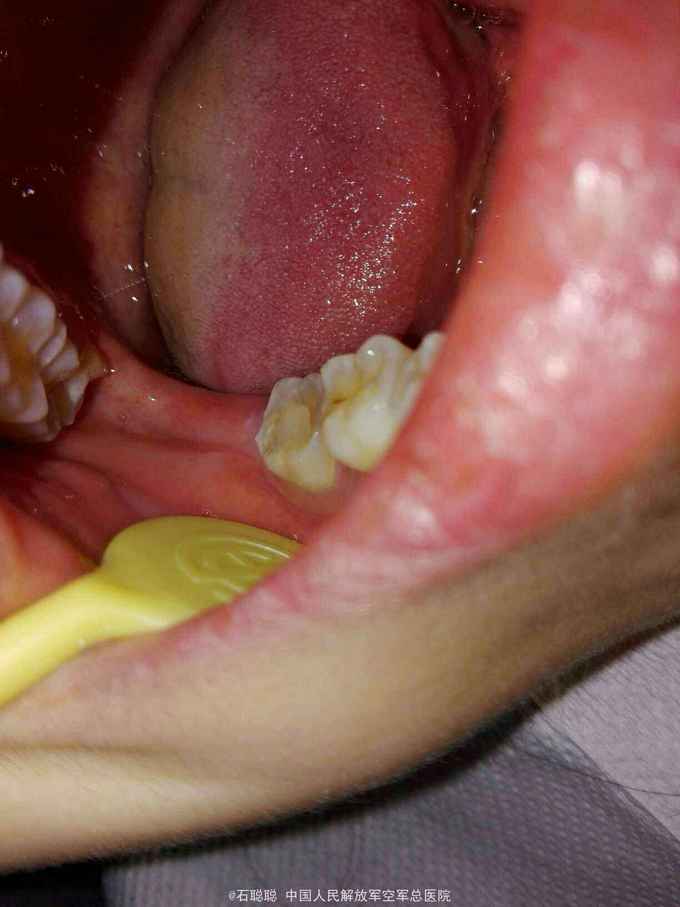

右下7全瓷嵌体冠修复

检查:47合面见白色暂封物完整在位,近中、远中、颊侧、舌侧壁厚度>2mm。咬合紧。叩痛-,无明显松动,牙龈未见明显异常,牙周探诊深度2mm。 根尖片:47根管内高密度充填影像,恰填,牙周膜、根尖区及根分叉未见异常

诊断:47牙体缺损 治疗计划:47全瓷嵌体冠修复 处置:47去除暂封,磷酸锌垫底,光固化覆合树脂充填,预备全瓷嵌体冠,取模,比色3M2,制作临时冠,调合,磨光,粘固 一周后复诊: 检查:临时冠完整在位,无松动,叩痛- 处置:去除47临时冠,试戴全瓷嵌体冠,调合,抛光,U200粘接 医嘱:勿用患牙咀嚼脆骨、坚果等过硬食物 口腔卫生宣教:巴斯刷牙法,牙线使用方法 不适复诊

讨论:这是常一例规的后牙根管治疗后要求修复的病历,患牙的对合略有伸长,咬合紧,尽管将对合做了降合处理,仍会降低龈合距离,削弱全冠的固位力,幸运的是47的四个轴壁均完整并且高度、厚度能满足制作嵌体冠的需要,可以利用髓腔制备固位形,明显改善了固位不足的状态。嵌体预备要点要满足轴壁无倒凹,有2-5度的合方外展,与牙冠就位道一致。